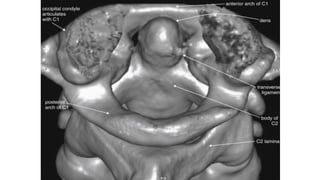

This three-dimensional reconstruction from computed tomography (CT) axial images focuses on the occipital–

cervical junction and the C1-2 (atlantoaxial) junction

The skull base has been cut away nearly completely in this

CT model, allowing the ring of C1 and its relationship to the

dens of C2 to be seen in detail.

C1 and C2 view of the normal cervical spine

This three-dimensional CT model is oriented with the observer looking cephalad along the anterior

surface of the cervical spine. A series of holes perforating the transverse processes of each vertebra

can be seen—the transverse foramen.

This three-dimensional reconstructionfrom computed tomography (CT) axial images focuses on the occipital– cervical junction and the C1-2 (atlantoaxial) junction

• 13.

The skull basehas been cut away nearly completely in this CT model, allowing the ring of C1 and its relationship to the dens of C2 to be seen in detail. C1 and C2 view of the normal cervical spine

• 15.

This three-dimensional CTmodel is oriented with the observer looking cephalad along the anterior surface of the cervical spine. A series of holes perforating the transverse processes of each vertebra can be seen—the transverse foramen.